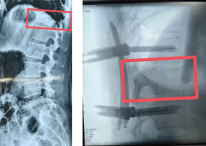

82岁高龄老人心脏“阀门”卡壳 西安市中心医院心内科三病区巧解“危局”

阳光讯(记者 郑亚雷)近日,西安市中心医院心血管内科三病区的手术室内,一场针对82岁高龄老人复杂心脏问题的“修瓣”手术紧张进行。最终,医生成功为老人植入该院首例SAPIEN 3人工瓣膜,让原本“卡壳”...